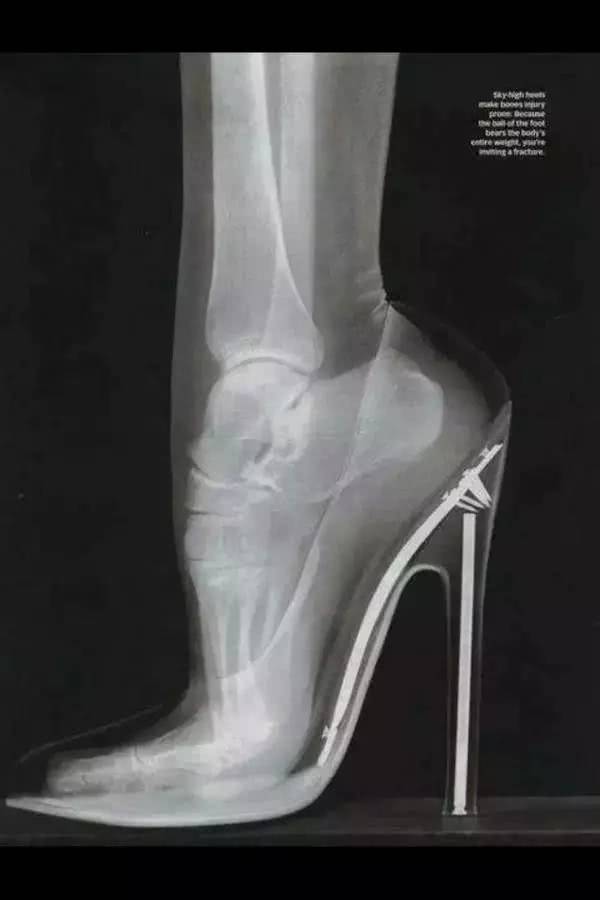

1、穿高跟鞋究竟有多辛苦?你的脚骨是这样子的